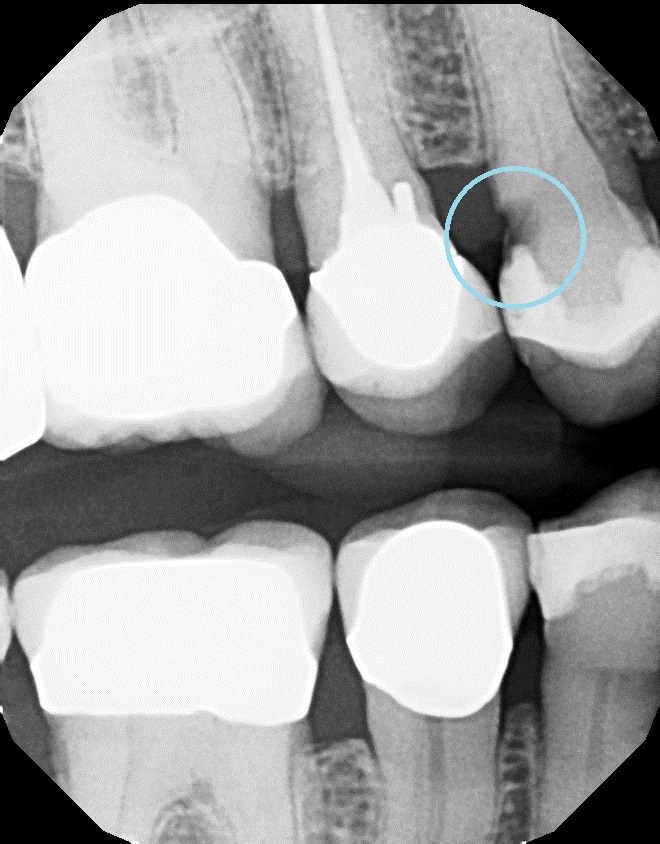

Dental Calculus Xray . Dental calculus is the plaque and sediment that has calcified or is calcifying on the tooth surface or prosthodontic body. You can’t remove it with brushing and flossing alone. Tartar (dental calculus) is hardened plaque. This narrative review presents a brief. Digital radiographs of teeth taken before extraction were modified using the following. We apply this technique for subgingival dental calculus detection and visualize the location of lesions.